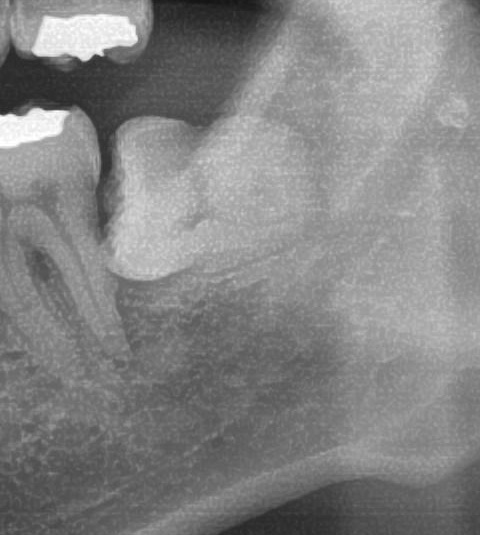

次にパノラマ写真を撮影してみると、左下の親知らずは歯茎の中で、手前の歯を押すように真横に生えているのが確認できました。